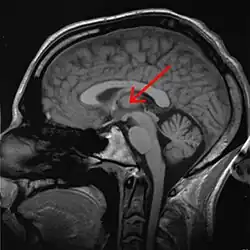

O tálamo é uma estrutura do cérebro que está localizada no diencéfalo, entre o córtex cerebral e o mesencéfalo, formada principalmente por substância cinzenta (núcleos de neurônios) do encéfalo. [1] São duas massas neuronais situadas na profundidade dos hemisférios cerebrais. Dentre suas funções estão a transmissão de sinais motores e sensitivos para o córtex , [2] além da regulação da consciência, sono e estado de alerta. Juntamente com os núcleos da base, o tálamo é uma estrutura importante para funções cognitivas como memória, atenção, seleção e monitoramento de informações.

O tálamo é um conjunto bem definido de vários núcleos de neurônios e forma uma parte maior do diencéfalo. Existem dois deles situados em posições simétricas, à esquerda e à direita, cada um covixem cerca de 1 cm de comprimento. Sua extremidade anterior é estreita e arredondada, e constitui a parede posterior do forame interventricular; a porção posterior é expandida e está acima do colículo superior; a superfície inferior situa-se continuamente ao tegmento do mesencéfalo; sua face medial está confrontada com a mesma do outro tálamo e contém uma região de comunicação com ele, a adesão intertalâmica, que está rodeada pelo terceiro ventrículo.

O tálamo contém diversos núcleos: anterior, dorsomedial, lateral dorsal e lateral posterior, pulvinar, ventral anterior, ventral lateral, ventral posterior lateral e medial, intralaminares, da linha média, reticulares, e os geniculados laterais e mediais.